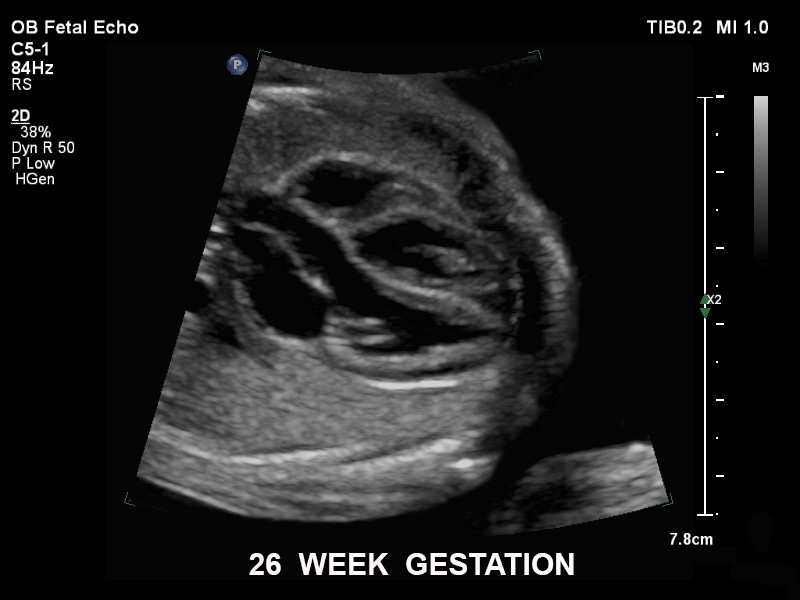

Überzeugende Bildgebung in allen Schwangerschafts­dritteln

Die EPIQ-Produktreihe mit ausgereiften Schallköpfen erfüllt die Anforderungen auch Ihrer anspruchsvollsten gynäkologischen Untersuchungen und während der gesamten Schwangerschaft.

• C5-1 PureWave-Breitband-Convex-Schallkopf für hohe Eindringtiefen in der Gynäkologie und der Geburtshilfe, für Patientinnen mit Schwangerschaftsdiabetes oder vorzeitigem Blasensprung